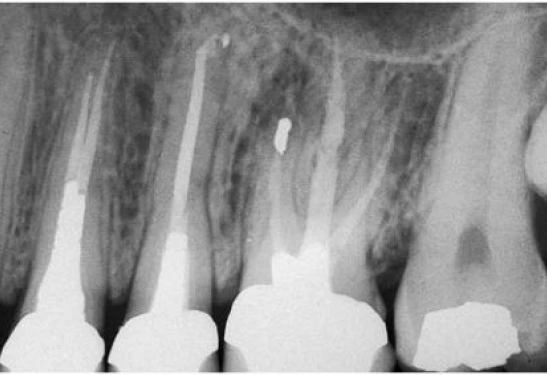

Răng cối lớn thứ nhất hàm trên

Cũng như răng cối lớn một dưới, răng này cũng thường cần điều trị nội nha. Nó cũng thường che đậy nhiều cạm bẫy và dẫn đến thất bại. Trong đa số các trường hợp, răng có ba chân với ba ống tủy độc lập nhau. Hiếm khi có hai chân với hai ống tủy (hình 11.53). Chân trong dài nhất và tròn theo mặt phẳng cắt ngang. Chân ngoài xa ngắn hơn một chút nhưng cũng hơi tròn theo mặt phẳng cắt ngang. Chân ngoài gần có thể dài hơn hoặc ngắn hơn nhưng dẹt hơn theo chiều gần xa.

Hình 11.53. A. Sàn tủy của răng #16 với hai miệng ống tủy, một ở trong và một ở ngoài. B. Phim sau điều trị: ống trong dài hơn và một ống ngoài, ống ngoài chia làm hai ống nhỏ hơn ở 1/3 chóp.

Chân trong thường cong ngoài và đoạn cong này không dễ đánh giá được trên phim X-quang (hình 11.54 A). Càng về phía chóp, đôi khi nó còn có một đoạn cong thứ hai ngược lại. Pineda và Kuttler nghiên cứu thấy rằng 81% chân trong của răng cối lớn thứ nhất trên cong, theo kinh nghiệm lâm sàng hai ông đồng ý rằng nên luôn nghĩ rằng chân này cong cho đến khi có bằng chứng chứng tỏ rằng không phải vậy (hình 11.54 B). Miệng ống tủy của chân trong nằm dưới múi trong gần. Chân răng thường có ống tủy phụ, đặc biệt là ở 1/3 chóp (hình 11.54 C, 11.55). Hiếm gặp trường hợp chân trong có hai ống tủy (hình 11.56), loại này chiếm tỉ lệ <2%, nhưng việc nhận thức được khả năng này cũng quan trọng. Kiểm tra cẩn thận sàn tủy có thể nhận thấy hình ảnh giải phẫu bất thường. Những trường hợp răng cối lớn thứ nhất trên với hai ống tủy trong hai chân trong (hình 11.57), hai ống tủy trong một chân răng giao nhau tại một lỗ chóp, và hai ống tủy trong cùng một chân răng với những lỗ chóp riêng biệt cũng đã được mô tả.

Hình 11.54. A. Hình ảnh răng #16 nhìn từ phía gần. Chú ý rằng đoạn cong ở chân trong, cong ra phía ngoài. B. Phim sau điều trị của răng #16. Chú ý chân trong có liên quan với xoang hàm trên. C. Ống trong của răng cối lớn thứ nhất hàm trên có một ống tủy phụ lớn ở phía xa.

Hình 11.55. Chú ý có nhiều ống tủy phụ ở chân trong cũng như chân ngoài gần (Courtesy of Dr. C. J. Ruddle)

Hình 11.56. A. Xoang tủy của răng #16 với hai ống trong. B. Phim trong lúc điều trị cho thấy hình ảnh hai dụng cụ trong hai ống trong. C. Phim trong lúc điều trị: hai ống trong và ống gần ngoài được trám bít lại. D. Phim sau điều trị.

Hình 11.57. A. Xoang tủy của răng #26 với hai ống trong ở hai chân răng. Lưu ý P: palatal canal (ống trong); MB: mesiobuccal canal (ống ngoài gần); DB: distobuccal canal (ống ngoài xa); DP: distopalatal canal (ống xa trong). B. Phim sau điều trị trên cùng răng này.

Chân ngoài xa thường thẳng nhưng nó có thể hơi cong nhẹ về phía gần hoặc xa. Trong đa số trường hợp nó có một ống tủy, miệng ống tủy không liên quan trực tiếp đến múi tương ứng mà thường nằm về phía trong hơn. Tuy nhiên có những trường hợp răng cối lớn trên có chân ngoài xa có hai ống tủy, ống xa trong ở phía trong so với ống tủy chính (hình 11.58).

Hình 11.58. A. Phim trước điều trị của răng #16 với năm ống tủy. B. Xoang tủy bộc lộ năm miệng ống tủy sau khi năm ống này đã được làm sạch và tạo hình. C. Đưa năm cây dụng cụ vào năm ống tủy (đưa năm dụng cụ vào chỉ để lấy ảnh làm tư liệu chứ không phải là đo chiều dài năm ống cùng lúc). D. Phim trong lúc điều trị. E. Hình ảnh các ống tủy chụm lại ở vùng chóp. Các ống tủy dường như không có những lỗ chóp riêng biệt. F. Phim sau điều trị.

Trong ba chân, chân ngoài gần có nhiều hình dạng giải phẫu nhất. Nó hoàn toàn dẹt theo chiều gần xa. Vì vậy ống tủy chân răng có hình dạng như dải băng, hoặc thường có hai ống tủy phân biệt. Tỉ lệ % có hai ống tủy theo mỗi tác giả khác nhau cũng khác nhau, nhưng tất cả đều nhất trí rằng: tỉ lệ này >50% [ 53% theo Hess, 60.7% theo Pineda và Kuttler, 64% theo Smith và Nosonowitz và Brenner, 69.4% theo Acosta Vigouroux và Trugeda Bosaans, 84% theo Aydosand Milano, 93% theo Stropko và 96,1% theo Kulid (Bảng I)]